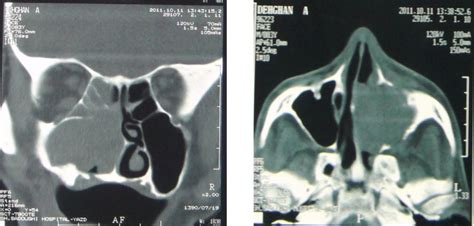

- A, Coronal And B, Axial Computerized Tomographs (ct) | Download ...